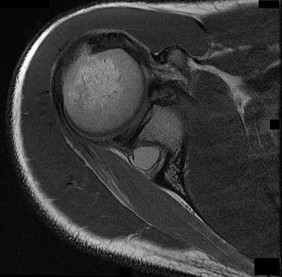

Question 33:

A 21-year-old collegiate rugby player presents with recurrent anterior shoulder instability. He has had 5 dislocations over the past year. A 3D reconstructed CT scan of the shoulder reveals an inverted-pear glenoid with an estimated 28% anterior inferior bone loss. Which of the following surgical interventions provides the most reliable biomechanical stability and lowest recurrence rate for this specific patient?

Correct Answer: Latarjet procedure

Explanation:

Anterior glenoid bone loss exceeding 20-25% (often described visually as an 'inverted pear' glenoid) is a critical threshold in anterior shoulder instability. Soft tissue procedures alone, such as arthroscopic or open Bankart repairs, have unacceptably high failure rates in this setting. The Latarjet procedure (transfer of the coracoid process with the attached conjoint tendon to the anterior glenoid) reconstructs the bony arc and provides a dynamic sling effect, making it the standard of care for critical glenoid bone loss.